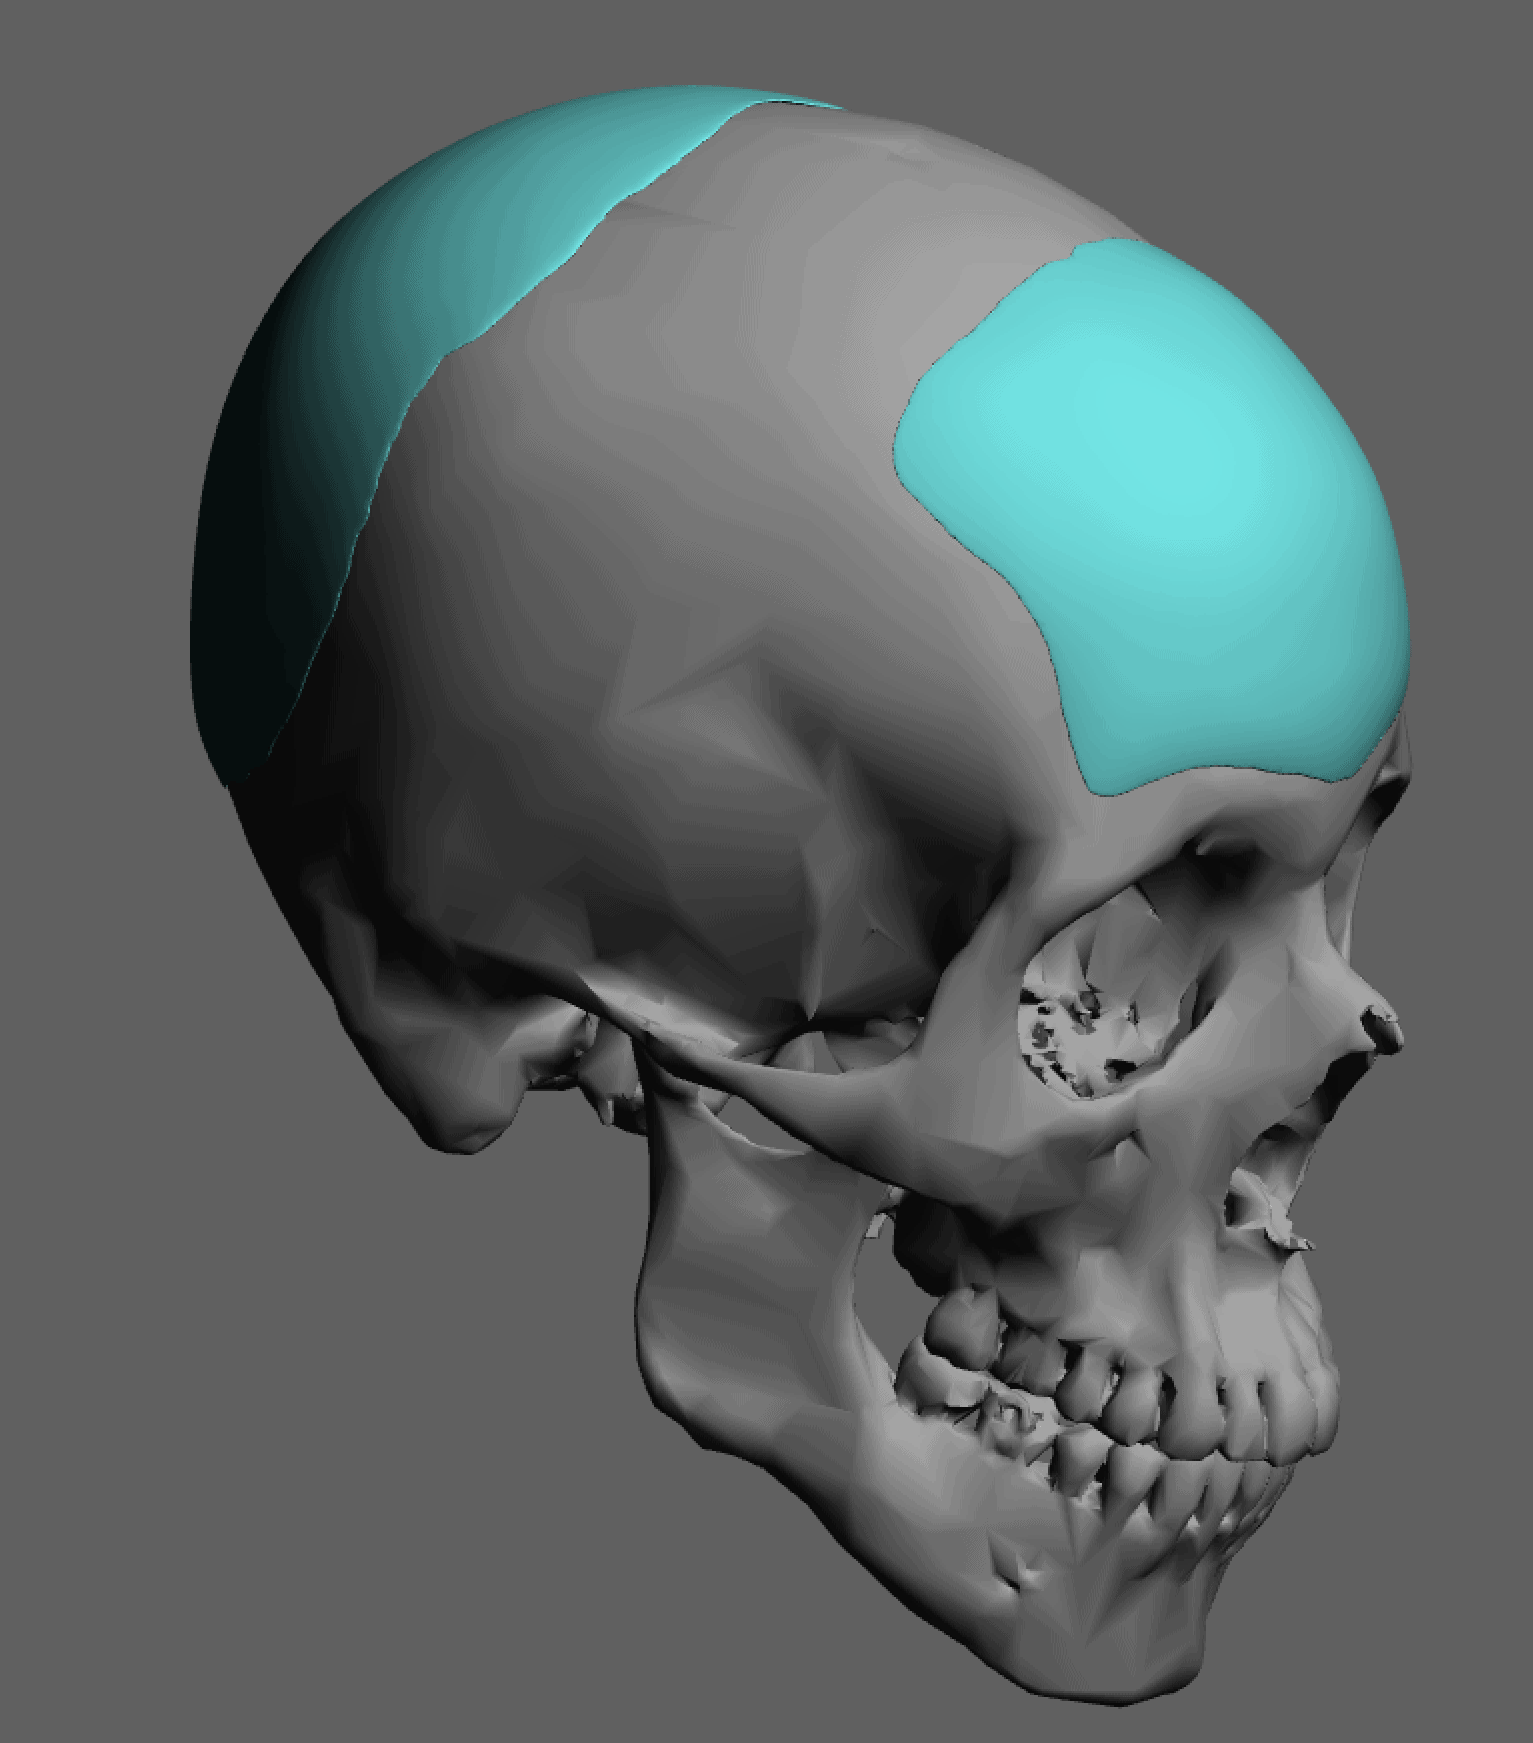

Severe narrowing skull deformity from prior sagittal craniosynostosis repair as an adult.

Complete replacement of entire skull by a custom implant with temporal fat injections.

Severe narrowing skull deformity from prior sagittal craniosynostosis repair as an adult.

Complete replacement of entire skull by a custom implant with temporal fat injections.